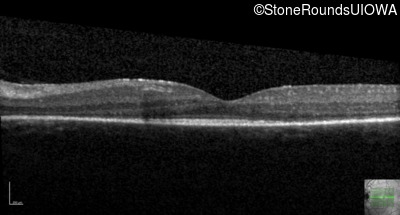

Optical Coherence Tomography - Left - 20/50 -3

Exemplar / OCT Stack